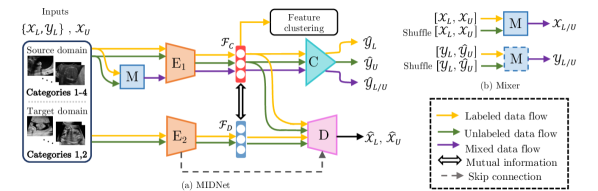

To solve this task, we propose MIDNet in combination with semi-supervised learning. The architecture of our model is shown in Fig. 4. Two independent encoders are utilized to respectively extract categorical features and domain features from labeled data and unlabeled data . The classifier is responsible for predicting class distributions from for both and while the decoder combines and for the reconstruction of input images. The mixer aims to linearly mix labeled and unlabeled samples so that the model is trained to show linear behavior between samples for further leveraging of unlabeled data. For representation disentanglement, mutual information between and is minimized to encourage to become domain-invariant and maximally informative for categorical classification. Feature clustering contains feature alignment and distance metric learning. Feature alignment aims at keeping the feature consistency between labeled images to promote the independence of . Distance metric learning considers inter-class relationships, which clusters similar samples while separating dissimilar samples to optimize for improving classification performance.

III-A Image reconstruction

The first step of MIDNet is to employ an Encoder-Decoder framework for independent extraction of two internal representations from the input data . Two encoders are built to respectively generate latent vectors that aim to represent categorical features and domain features , where and . The decoder is utilized to guarantee that the combination of these features is capable of recovering original input data, where . Here, and are the parameters of , respectively. The cost function of this reconstruction is

We concatenate layers between and to integrate high-frequency features from into the reconstruction, which helps to contain valid information instead of noise. This image reconstruction extracts two groups of features from internal representations of original data. The rest of our networks are designed and trained to enable to only contain categorical information, thus becoming separated from that only contains domain information.

III-B Classification

We use a classifier to predict labels for labeled data, which encourages to be maximally informative about categorical classification. and are updated by minimizing the cross-entropy loss

Here refers to the parameters of . At the same time, predicts the class distribution of the unlabeled data as . The predicted will be utilized in SSL-based regularization (Sec. III-E). The classifier on its own is unlikely to ensure that categorical features are domain-invariant. This is because the training objective in Eq. 2 only ensures that contains as much information as possible for the target classification task.

III-C Mutual information disentanglement

III-D Feature clustering

To introduce the supervision from labeled samples for an enhanced disentanglement, we aim at aligning categorical features between source and target domains. We hypothesize that categorical features of a certain category are supposed to be consistent between different domains. Therefore, we further enhance to be domain-invariant by minimizing the distance of categorical features between source domain and target domain for samples in with

where is the number of samples in category , and are the categorical features of the th sample from category in the source domain and the target domain, respectively. This loss is computed within categorical features in order to enhance mutual information disentanglement. This is different from feature alignment in other domain adaptation approaches (e.g., [58, 39]), where the feature alignment directly aligns the whole latent features of inputs. In addition, our categorical feature alignment uses the Frobenius norm as the distance metric since labeled samples from both domains are available, whereas many other domain adaptation approaches (e.g., [62, 38]) utilize Maximum Mean Discrepancy (MMD) [7] to diminish the discrepancy between a labeled source domain and an unlabeled target domain.

After feature alignment, We additionally consider inter-class relationships. To further cluster samples from the same category and separate samples from different categories in the latent space, we introduce distance metric learning with triplet loss [56] on of labeled images from both domains,

Here, is the squared Euclidean distance. is the categorical feature of one query sample from category . and are respectively categorical features of one support sample from the same category and one negative sample from a different category , where . The selection of the query sample, the support sample and the negative sample is essential for converge. For implementation, we utilize the online semi-hard triplet mining strategy in [56].

Considering both feature alignment and separation, the feature clustering loss is

where is a hyper-parameter. In practice, we mainly focus on feature alignment and set as the proposed method because feature alignment is the key point to keep consistency between both domains. In our applications, we conduct both experiments, i.e., with and without , to evaluate the importance of inter-class relationships.

III-E SSL-based regularization

Conventional fully supervised learning requires a large number of annotated input images with categorical labels and domain labels. However, in practice, labeled data is not easily available at any granularity. Berthelot et al. [6] propose a SSL-based method, MixMatch, integrating unlabeled data during training to reduce the dependency on labeled data. We adopt a simplified MixMatch using a mixer to leverage unlabeled data. As shown in Fig. 4 (b), is utilized to linearly combine two random samples and their corresponding labels from labeled data and unlabeled data by

where , . Here, , . is the concatenation of and . is the shuffled along the batch axis. Similarly, with , and . Note that is the collection of the predicted labels for unlabeled data according to Sec. III-B. We denote that , . The goal of this SSL-based regularization is to encourage the linear behavior of the classifier, and thus the objective function is

where is the predicted label of via classifier .